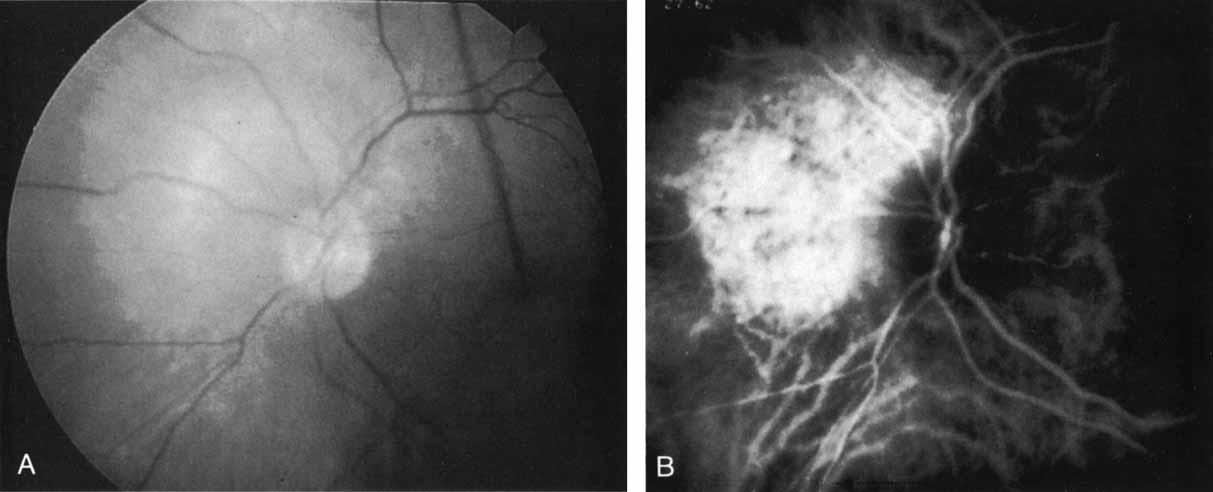

Harada disease, an inflammatory condition often affecting both eyes in young patients, is typified on fluorescein angiography by multiple focal areas of hypofluorescence early in the study, followed by late confluent leakage in the later phases (Fig. 17A, 17B, and 17C). With ICG angiography, multiple focal hypofluorescent spots are seen in the early phases, many more than were noted on the fluorescein study64,68 (Fig. 17D). The process extends further than the clinically or angiographically involved areas. The spots vary in size and density but appear to be well circumscribed. In the later phases of the ICG study, there is generalized hypofluorescence, with masking of the background choroidal fluorescence by the neurosensory detachment (Fig. 17E). This masking effect covers a large area, with inferior round margins confirming the gravitating nature of the neurosensory elevation. In addition, focal hyperfluorescent spots can be seen, possibly representing sites of active chorioretinal leakage or inflammation. In one patient, steroid therapy resulted in a marked resolution of clinical findings within 1 week.68 Repeat ICG angiography revealed a marked resolution of the hypofluorescent lesions as well as the hyperfluorescent spots. New areas of hypofluorescence did appear, the significance of which remains undetermined (Fig. 17E).

Fig. 17 Clinical photograph of a patient with Harada disease demonstrating multiple serous elevations of the retinal pigment epithelium with an overlying shallow neurosensory detachment. B. Early-phase fluorescein angiogram demonstrating hypofluorescent spots at the site of localized inflammation. C. Late-phase fluorescein study demonstrating hyperfluorescence in a confluent nature in the central macula. D. Early-phase indocyanine green (ICG) study demonstrating hypofluorescent spots in the central macular region. Note that the lesions are more numerous and more widely distributed than noted on clinical or fluorescein angiographic examination. E. Late-phase ICG study demonstrating extensive areas of confluent hypofluorescence. Note the curvilinear and gravitating nature of these hypofluorescent lesions, which are believed to represent blocked fluorescence from the shallow neurosensory detachment. Focal hyperfluorescent spots are noted within this region, which may represent areas of more active inflammation.